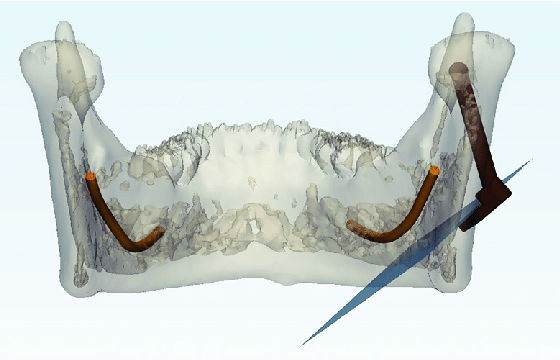

... why not going for a cut like below to fix so-called "inward gonions" ? You can then imagine a variety of movements and segmentations to attain the desired result, akin to chin osteotomy.

... why not going for a cut like below to fix so-called "inward gonions" ? You can then imagine a variety of movements and segmentations to attain the desired result, akin to chin osteotomy.